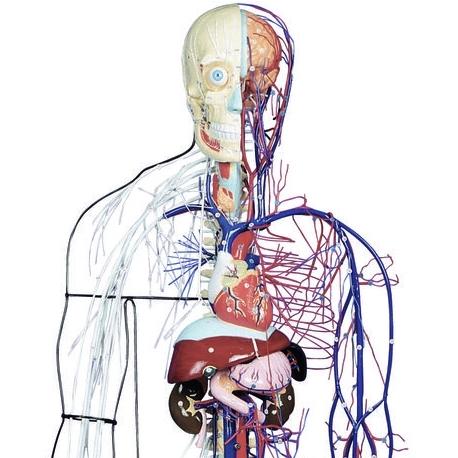

公式ファッションブランド通販サイト and Nervous Full-Figure Circulatory GTSimulators.com – System アート・デザイン・音楽

公式ファッションブランド通販サイト and Nervous Full-Figure Circulatory GTSimulators.com – System アート・デザイン・音楽

Full-Figure Nervous and Circulatory System – GTSimulators.com,

Full-Figure Nervous and Circulatory System – GTSimulators.com, Jisbar | Two Tone Kaws (2023) | Available for Sale | Artsy,